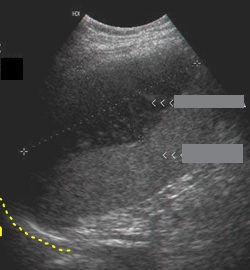

Identify this image.

Splenic aneurysm